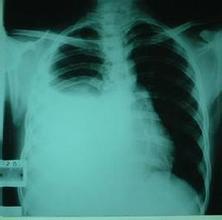

肿瘤性胸腔积液亦称恶性胸腔积液,大多数病例可以在胸腔积液中找到恶性细胞,如果胸腔积液伴纵隔或胸膜表面转移性结节,无论在胸腔积液中能否找到恶性细胞,均可以诊断恶性胸腔积液。